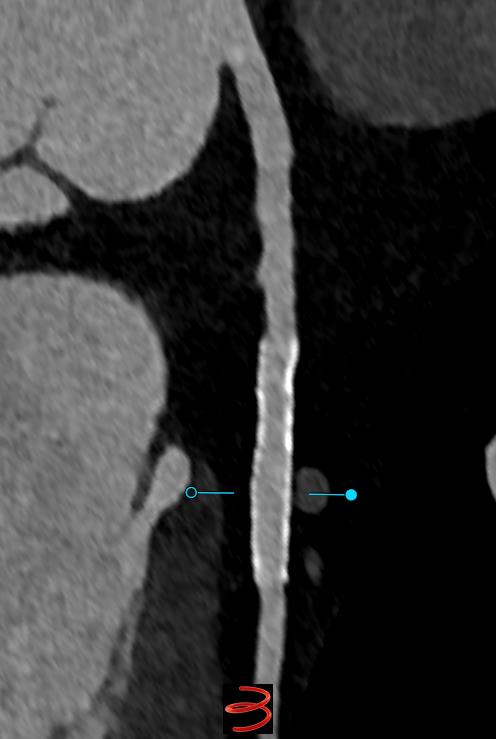

Ultra-high resolution #yesCCT imaging from the Naeotom Alpha. 0.2 mm recon , Bv56 kernel. No need for invasive angiography. St. Francis Hospital & Heart Center Heart_SCCT Juan Lopez-Mattei, MD Ryan P. Daly, MD Dr. Purvi Parwani Dr Andrew D. Choi Akhil Narang, MD